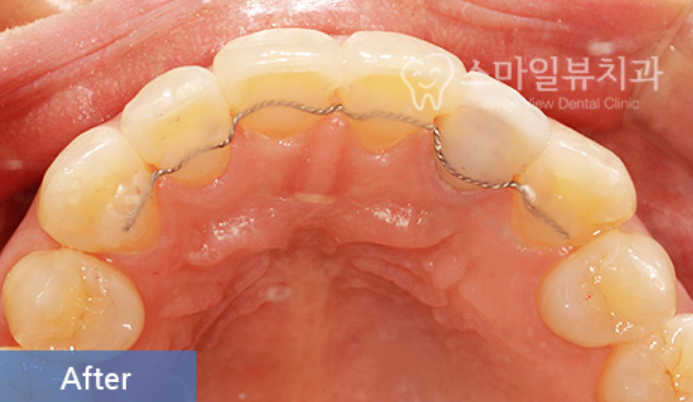

신논현역 치과 스마일 뷰에서 진행하는 설측 부분교정은 교정이 필요한 치아 안쪽에만

장치를 붙여서 치아를 이동하는 방법이에요.

치아 전체에 장치를 붙여서 치아를 이동하는 것보다는 훨씬 수월하고 시간도 짧고

치아 몇 개에만 장치가 들어가니 비용도 그만큼 적겠지요?

특히 신논현역 치과 스마일 뷰에서 많은 분들이 진행하는 설측 부분교정은

일부러 말하지 않으면 주변 사람들이 전혀 인식하지 못할 만큼 감쪽같이 진행할 수 있답니다.

신논현역 치과 스마일 뷰에서 설측 치아 부분교정을 진행하신 분들의 만족도는

생각보다 굉장히 좋습니다.